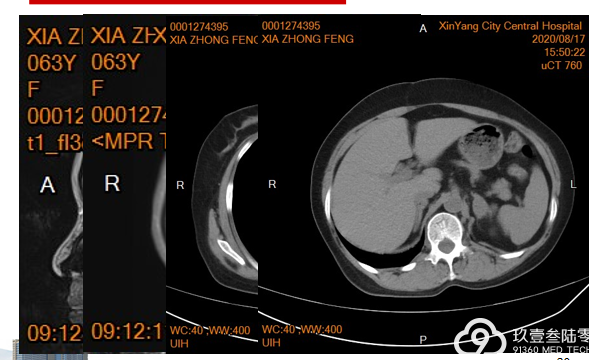

最后,是来自信阳市中心医院王贝教授,为我们带来一例肺癌患者的全程治疗分享。

患者 女 61岁 无吸烟史

2018-06出现咳嗽,刺激性干咳,偶有痰中带血,伴胸闷、心悸,在新县人民医院行胸部CT示:左肺舌叶周围性肺癌,建议结合病理学检查。予以抗感染治疗后出院,期间症状反复出现;

2018-10出现胸闷、胸痛症状,继续在当地医院治疗(具体不详),症状未见减轻。

2018-11-22来我院行胸腹部CT示: